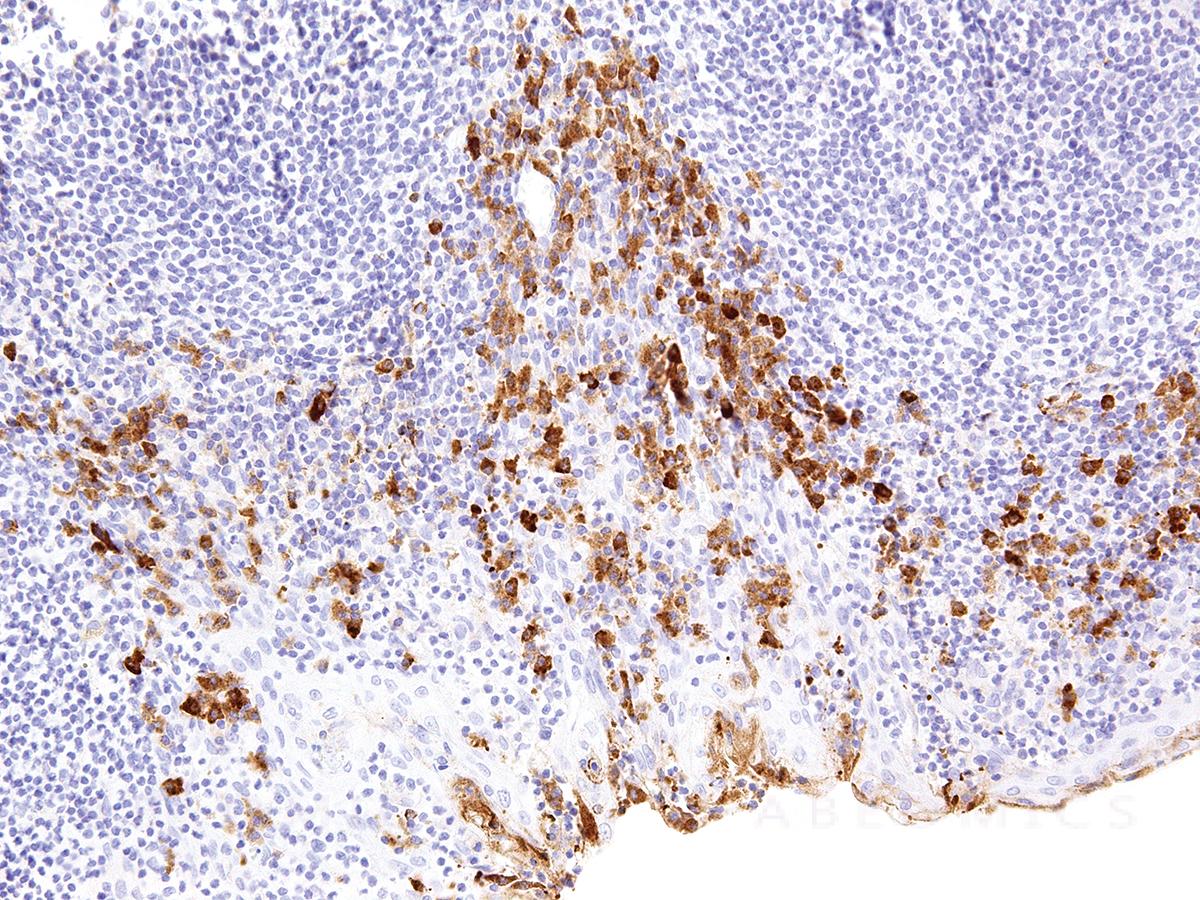

Figure 1: Immunohistochemical analysis of CTLA-4 (Clone: IHC004) on Tonsil